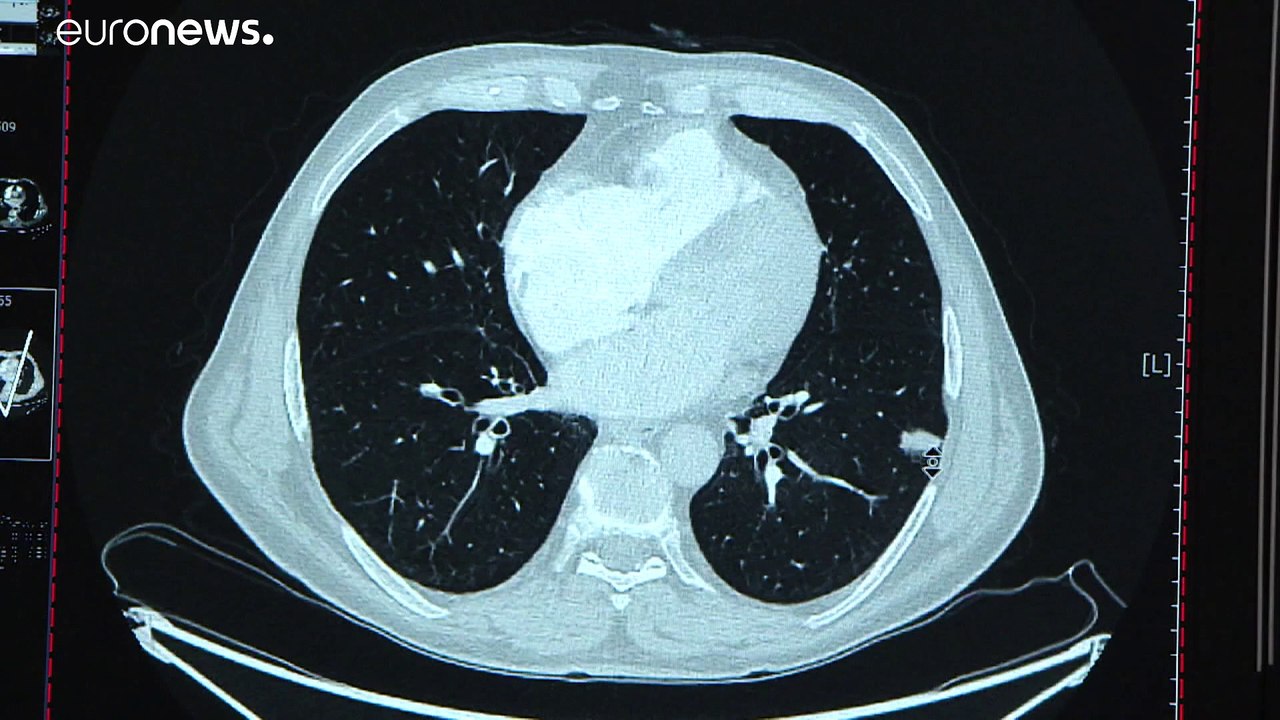

Wissenschaftler aus dem französischen Nizza haben eigenen Angaben zufolge einen neuen Test zur frühzeitigen Erkennung von Lungenkrebs entwickelt. Damit soll es in einigen Jahren möglich sein, die Krankheit per Blutabnahme zu diagnostizieren, lange bevor sie auf klassischen Röntgenaufnahmen zu erkennen ist.